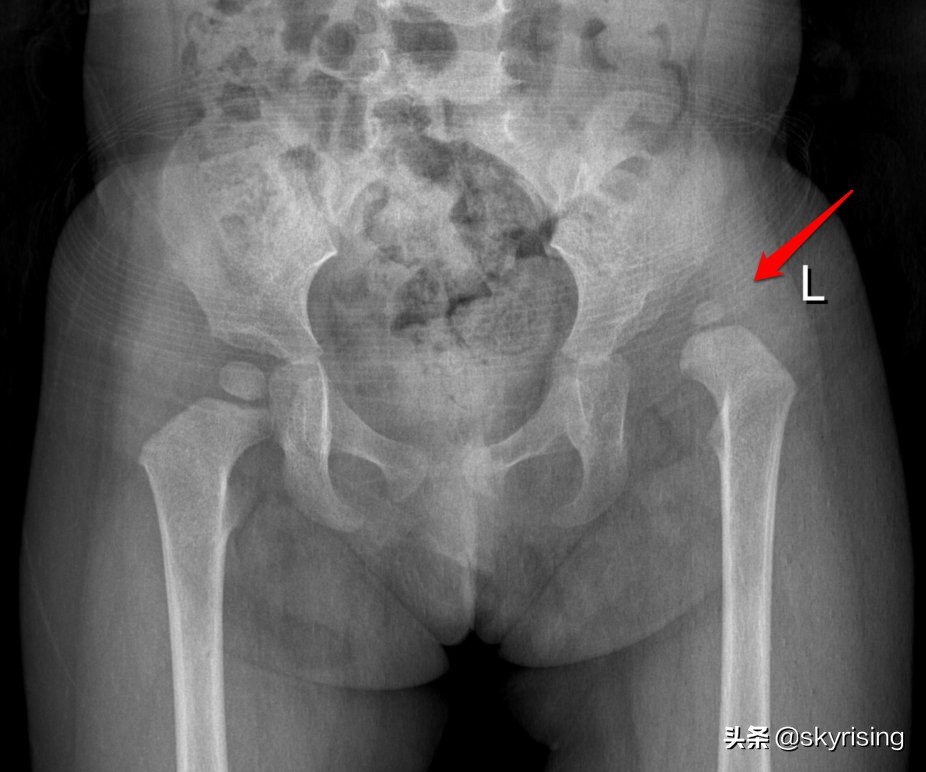

女性,11月,家人发现双下肢不对称就诊。DR影像如图:

左侧髋臼形态欠规整,髋臼角增大,红色箭头所示左侧股骨头骨骺较对侧细小,位于Perkin方格外上象限,沈通线及Calve线欠连续。提示左侧髋关节先天发育不良并脱位。